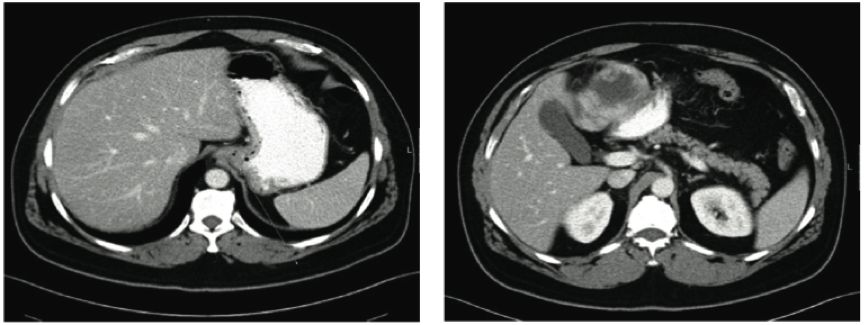

这是一篇关于伊马替尼治疗GIST皮肤不良反应的短篇通讯。1位GIST肝转移的患者术后接受了伊马替尼(格列卫)的治疗,4个月后出现了后背和腹部皮肤的进行性、非瘙痒的鳞屑痂(见附图),皮肤活检提示表皮层的棘层松解,微生物检测阴性,免疫荧光提示细胞间显著IgG沉积伴表皮上层C3沉积,故诊断为伊马替尼相关的落叶型天胞疮,经过暂停伊马替尼治疗并口服强的松龙及咪唑硫嘌呤1个月后,患者症状得以改善。在重头应用伊马替尼后,患者再次出现背部类似皮肤改变,因此予以永久停用伊马替尼并改为舒尼替尼,同时口服强的松龙后,患者皮肤症状得以缓解,在其后2年的随访中,患者未再出现皮肤病变。